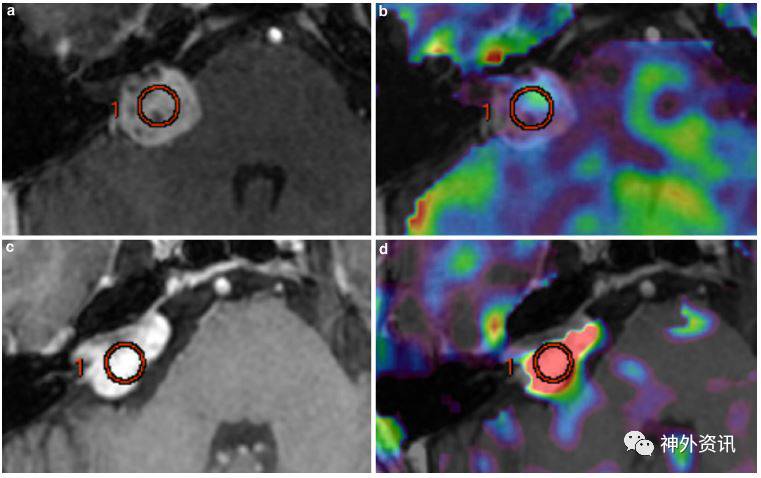

图2. 鞍区垂体腺瘤和脑膜瘤特征。注:MRI-T1加权冠状面对比:a、c图显示两均匀增强的鞍区肿瘤。CBF图显示:b为非富血流灌注肿瘤,低肿瘤-正常组织灌注比(nTBF=0.82),诊断垂体腺瘤;d为富血流灌注肿瘤,高肿瘤-正常组织灌注比(nTBF=5.35),诊断脑膜瘤。